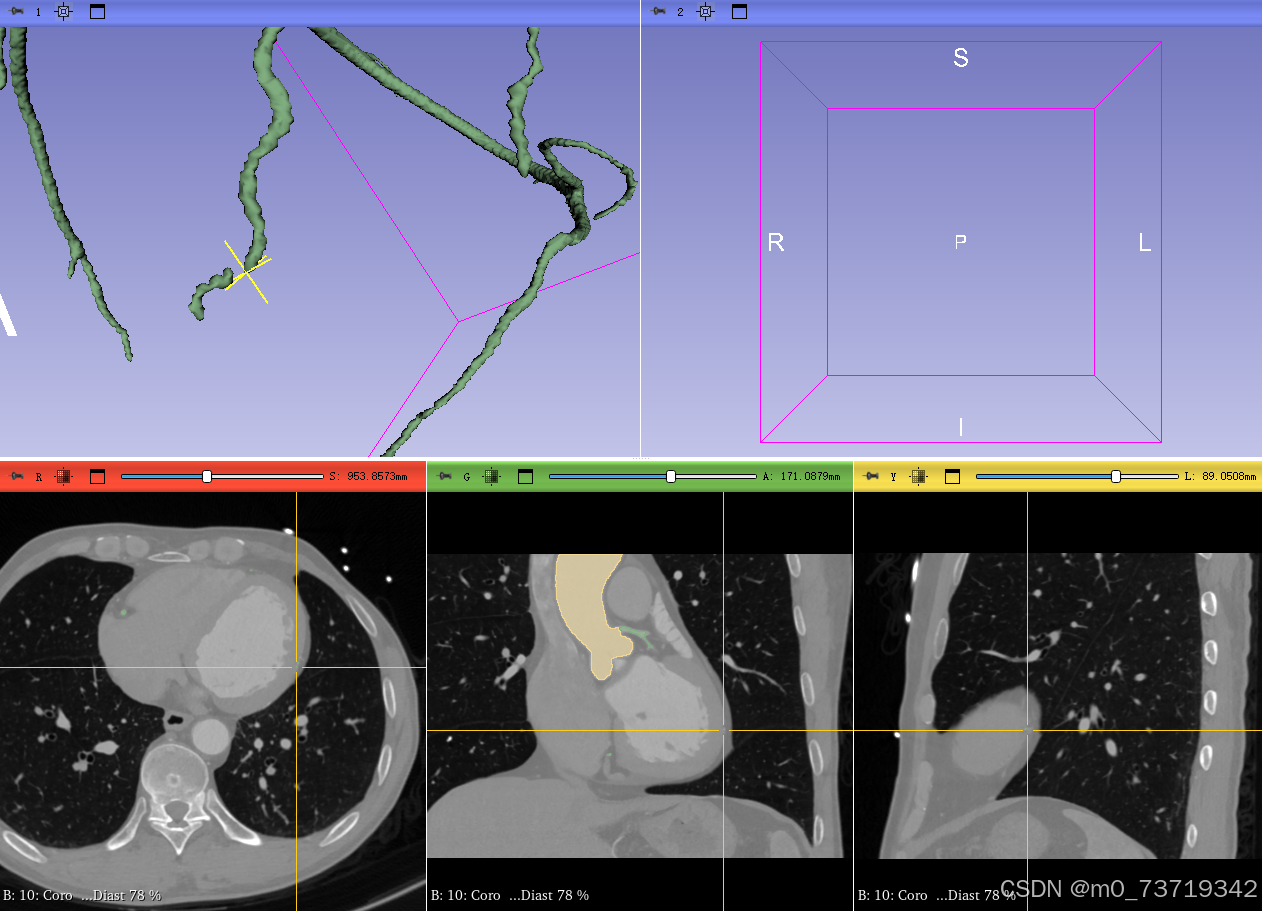

通过三维图像观察冠脉断点,在二维图像中进行补全

在三个视图中滚动观察是否有从已标注冠脉分出去的漏标冠脉进行补全

滚动前

滚动后明显漏标